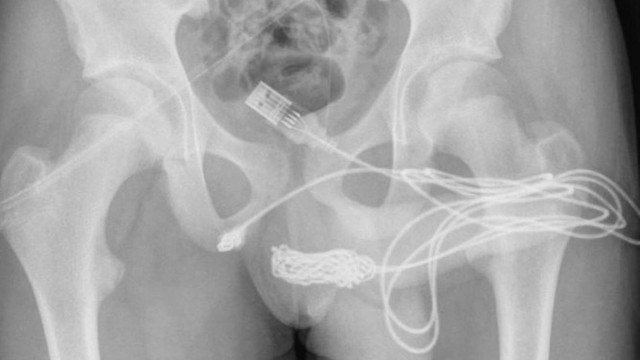

Jovem é operado após inserir cabo USB no pênis para tentar medir órgão

Um jovem de 15 anos, que mora em Londres, na Inglaterra, passou por uma cirurgia de emergência para tirar um cabo USB do pênis. Ele queria usar o fio para medir o tamanho do órgão. A história foi divulgada pela revista médica “Urology Case Reports”

.O adolescente tentou tirar o cabo sozinho e com ajuda da família, mas começou a urinar sangue e teve que ir pro pronto-socorro.Inicialmente a equipe tentou tirar o cabo com ferramentas especiais, mas não foi possível. Então ele foi reavaliado, com exames de raio-x, e encaminhado para cirurgia.O cabo só foi retirado depois que os cirurgiões cortaram os músculos ao redor do pênis do jovem.